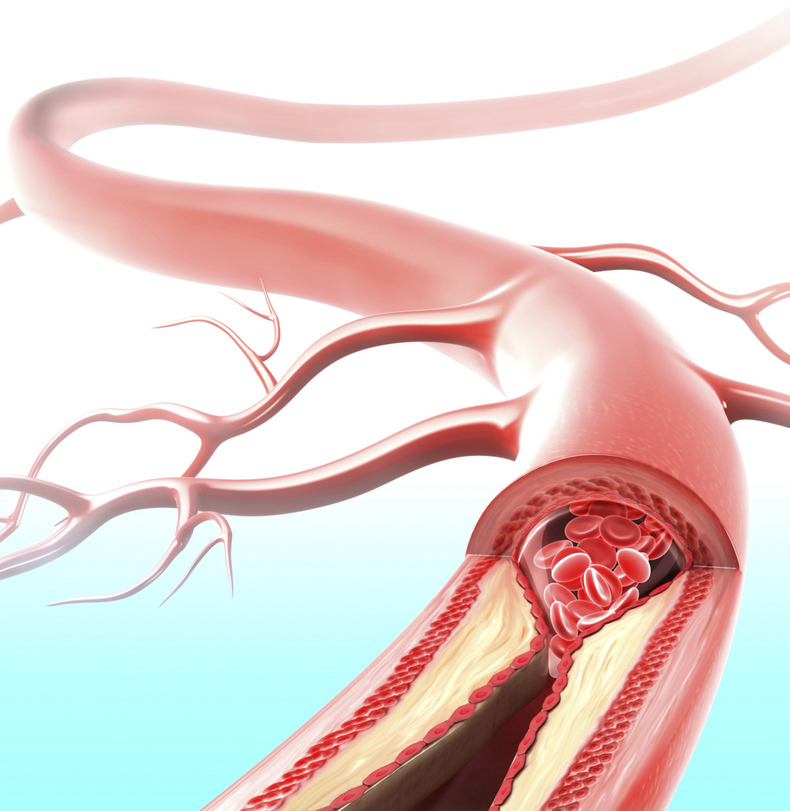

Хроническая окклюзия артерий: причины, симптомы и лечение